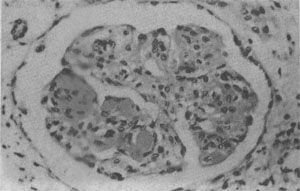

狼疮性肾小球肾炎

图4-10 狼疮性肾小球肾炎

肾小球毛细血管丛节段性纤维素样坏死,伴系膜细胞增生;间质炎细胞浸润